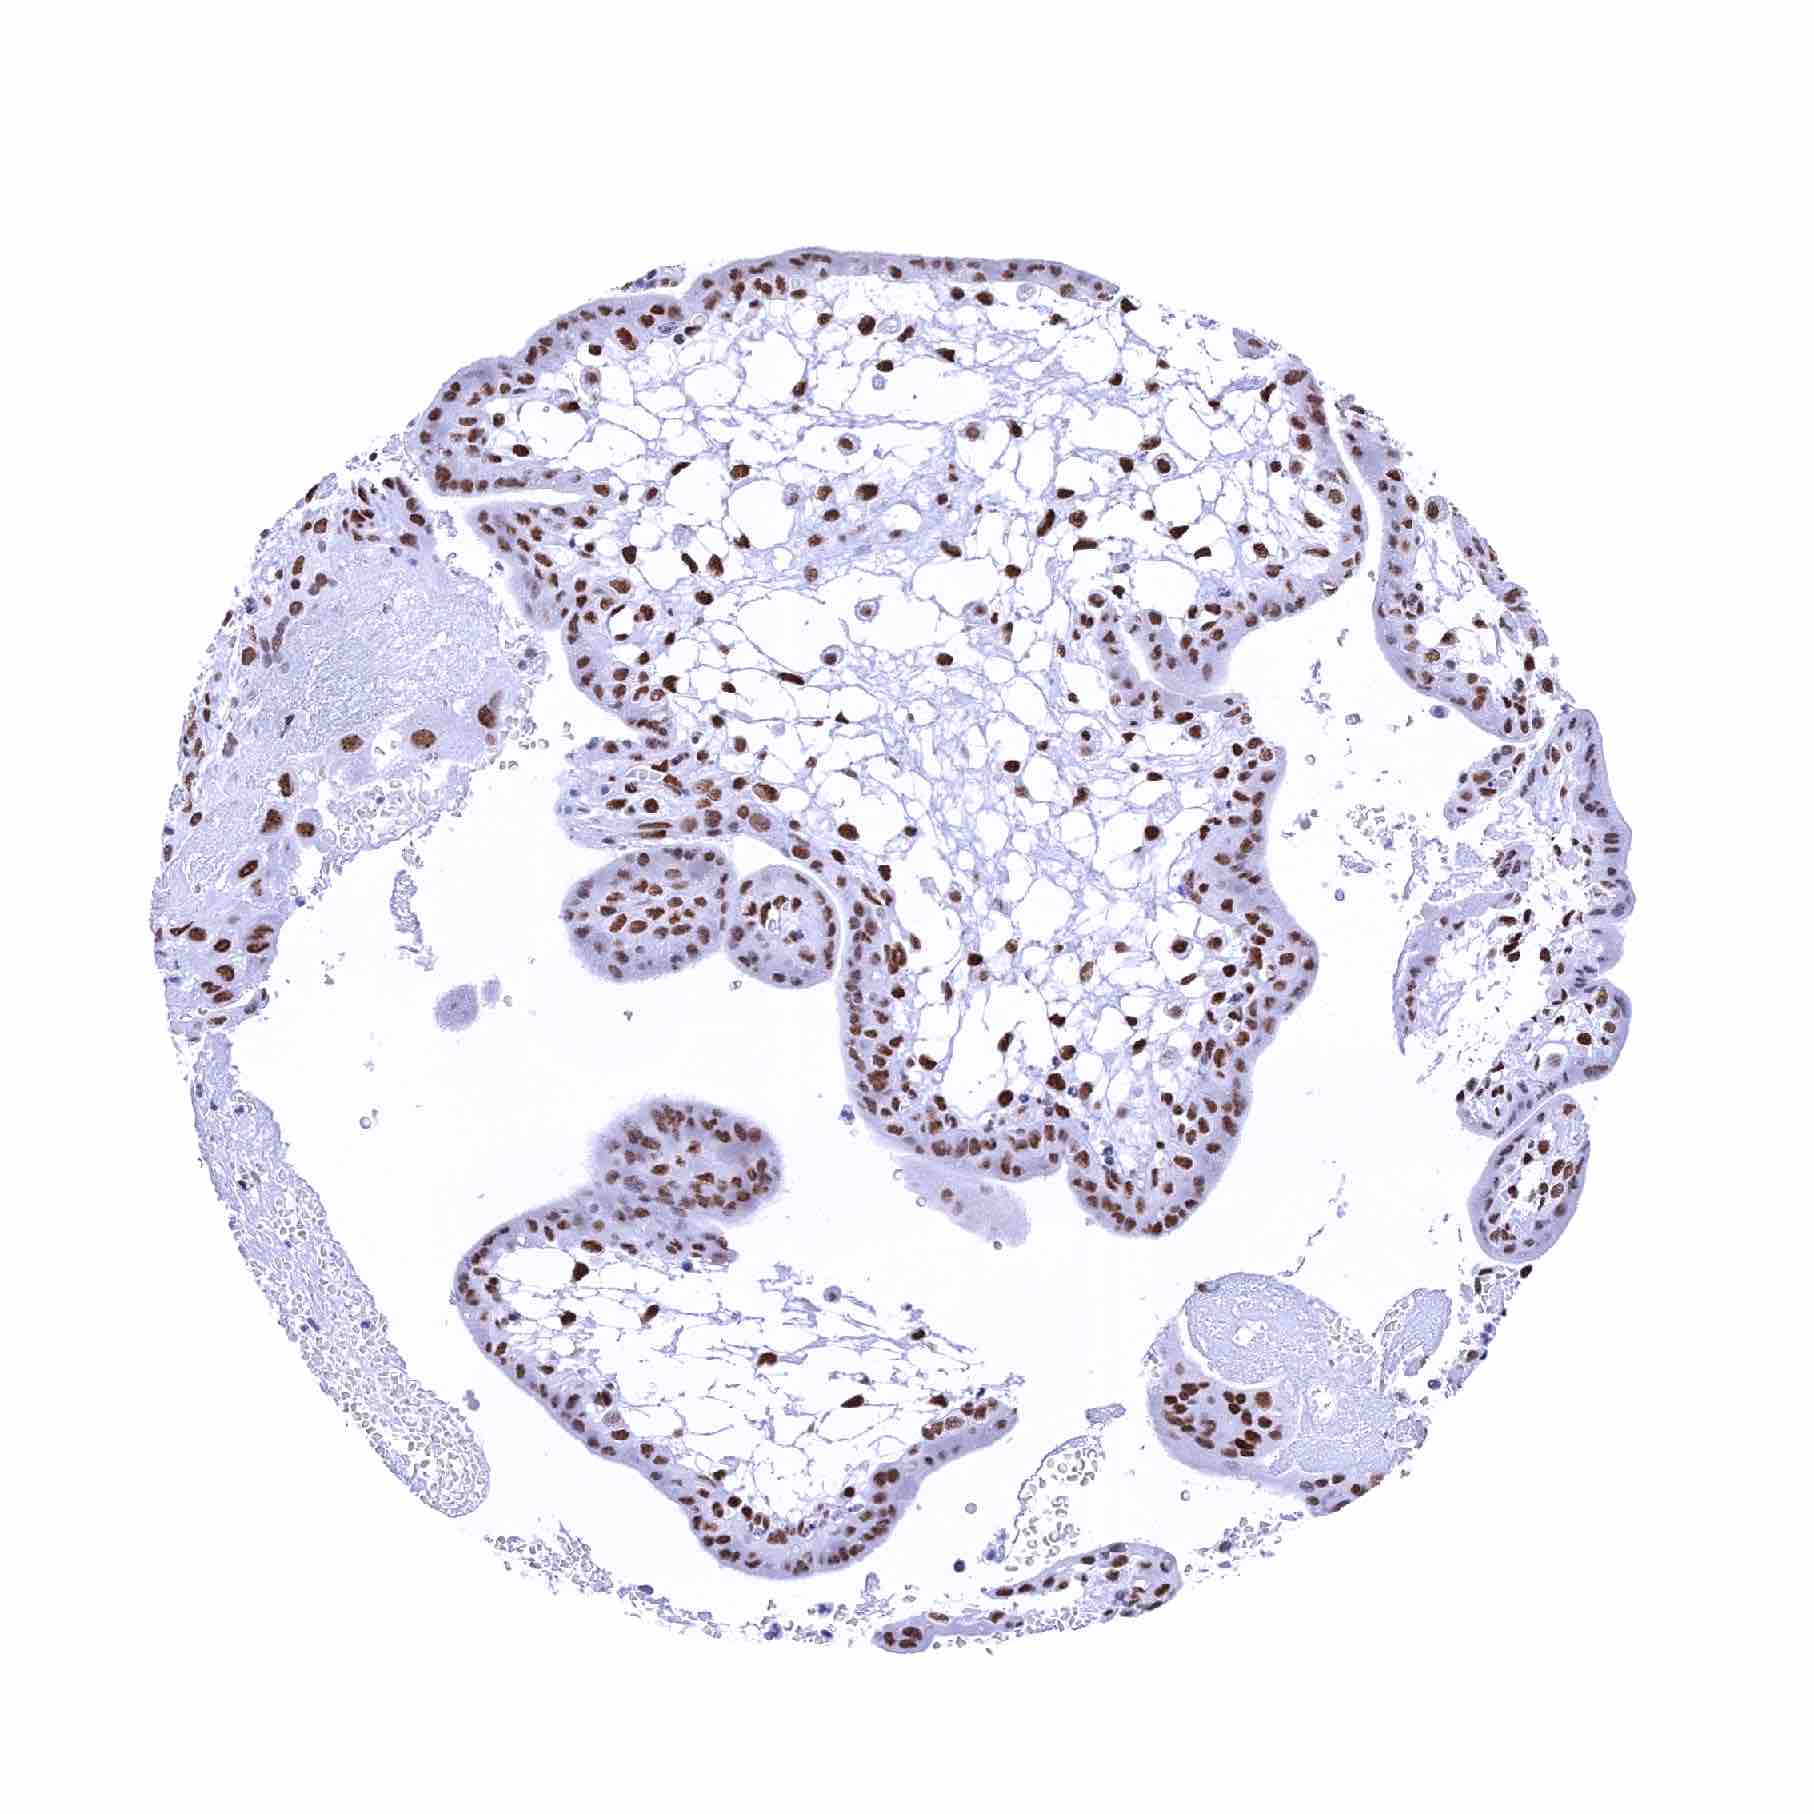

Normal Tissue Gallery- GTX640556

53BP1 antibody [HMV324] HistoMAXTM

Pancreas – Nuclear 53BP1 staining is particularly strong in islet cells